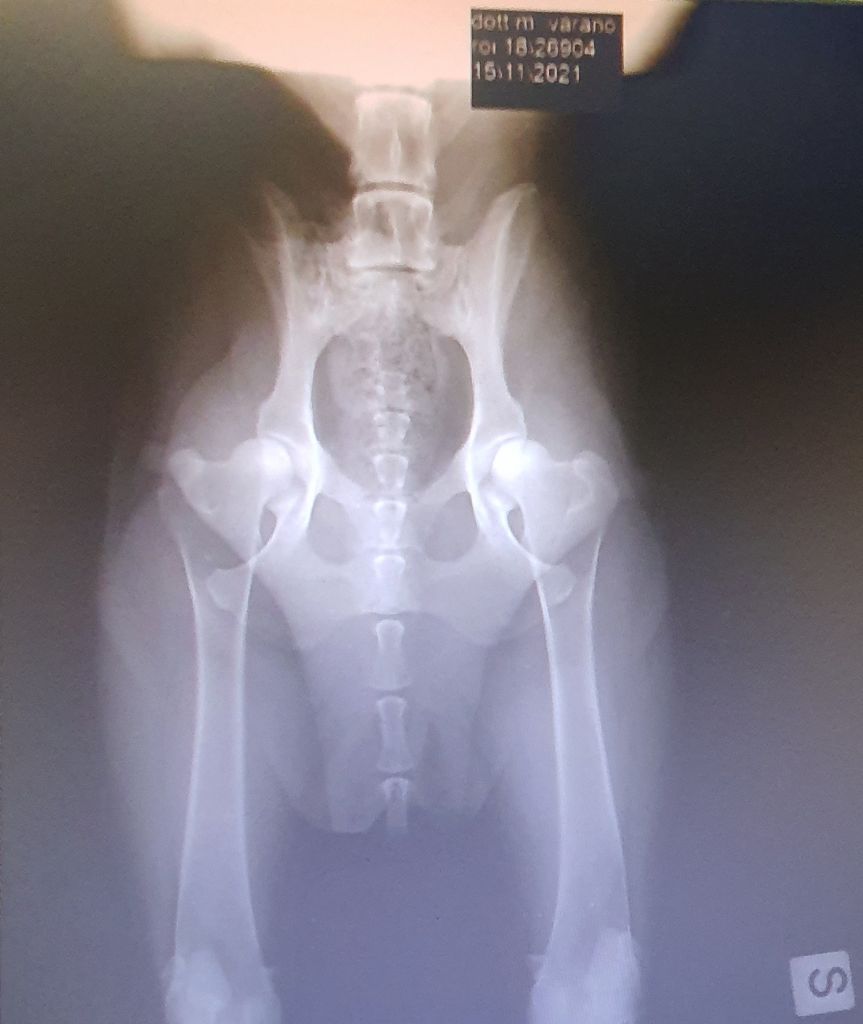

MAIA des Gardiens de Rome (esente da Displasia) radiografie ufficiali